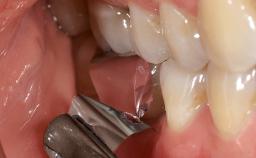

Paolo Casentini demonstrates that peri-implantitis can be successfully treated even at an advanced stage. He discusses a case in which the existing implants and prostheses were both retained while regenerating the defect and creating a band of keratinized tissue. A 69-year-old female patient was referred by her general dentist for evaluation of a recurrent infection at previously placed and restored implants in the posterior left mandible. The patient’s chief complaint was recurrent swelling and pain in the molar region of the left posterior mandible with discomfort during brushing in the same area. The patient reported receiving two implants (36 and 37) nine years earlier.